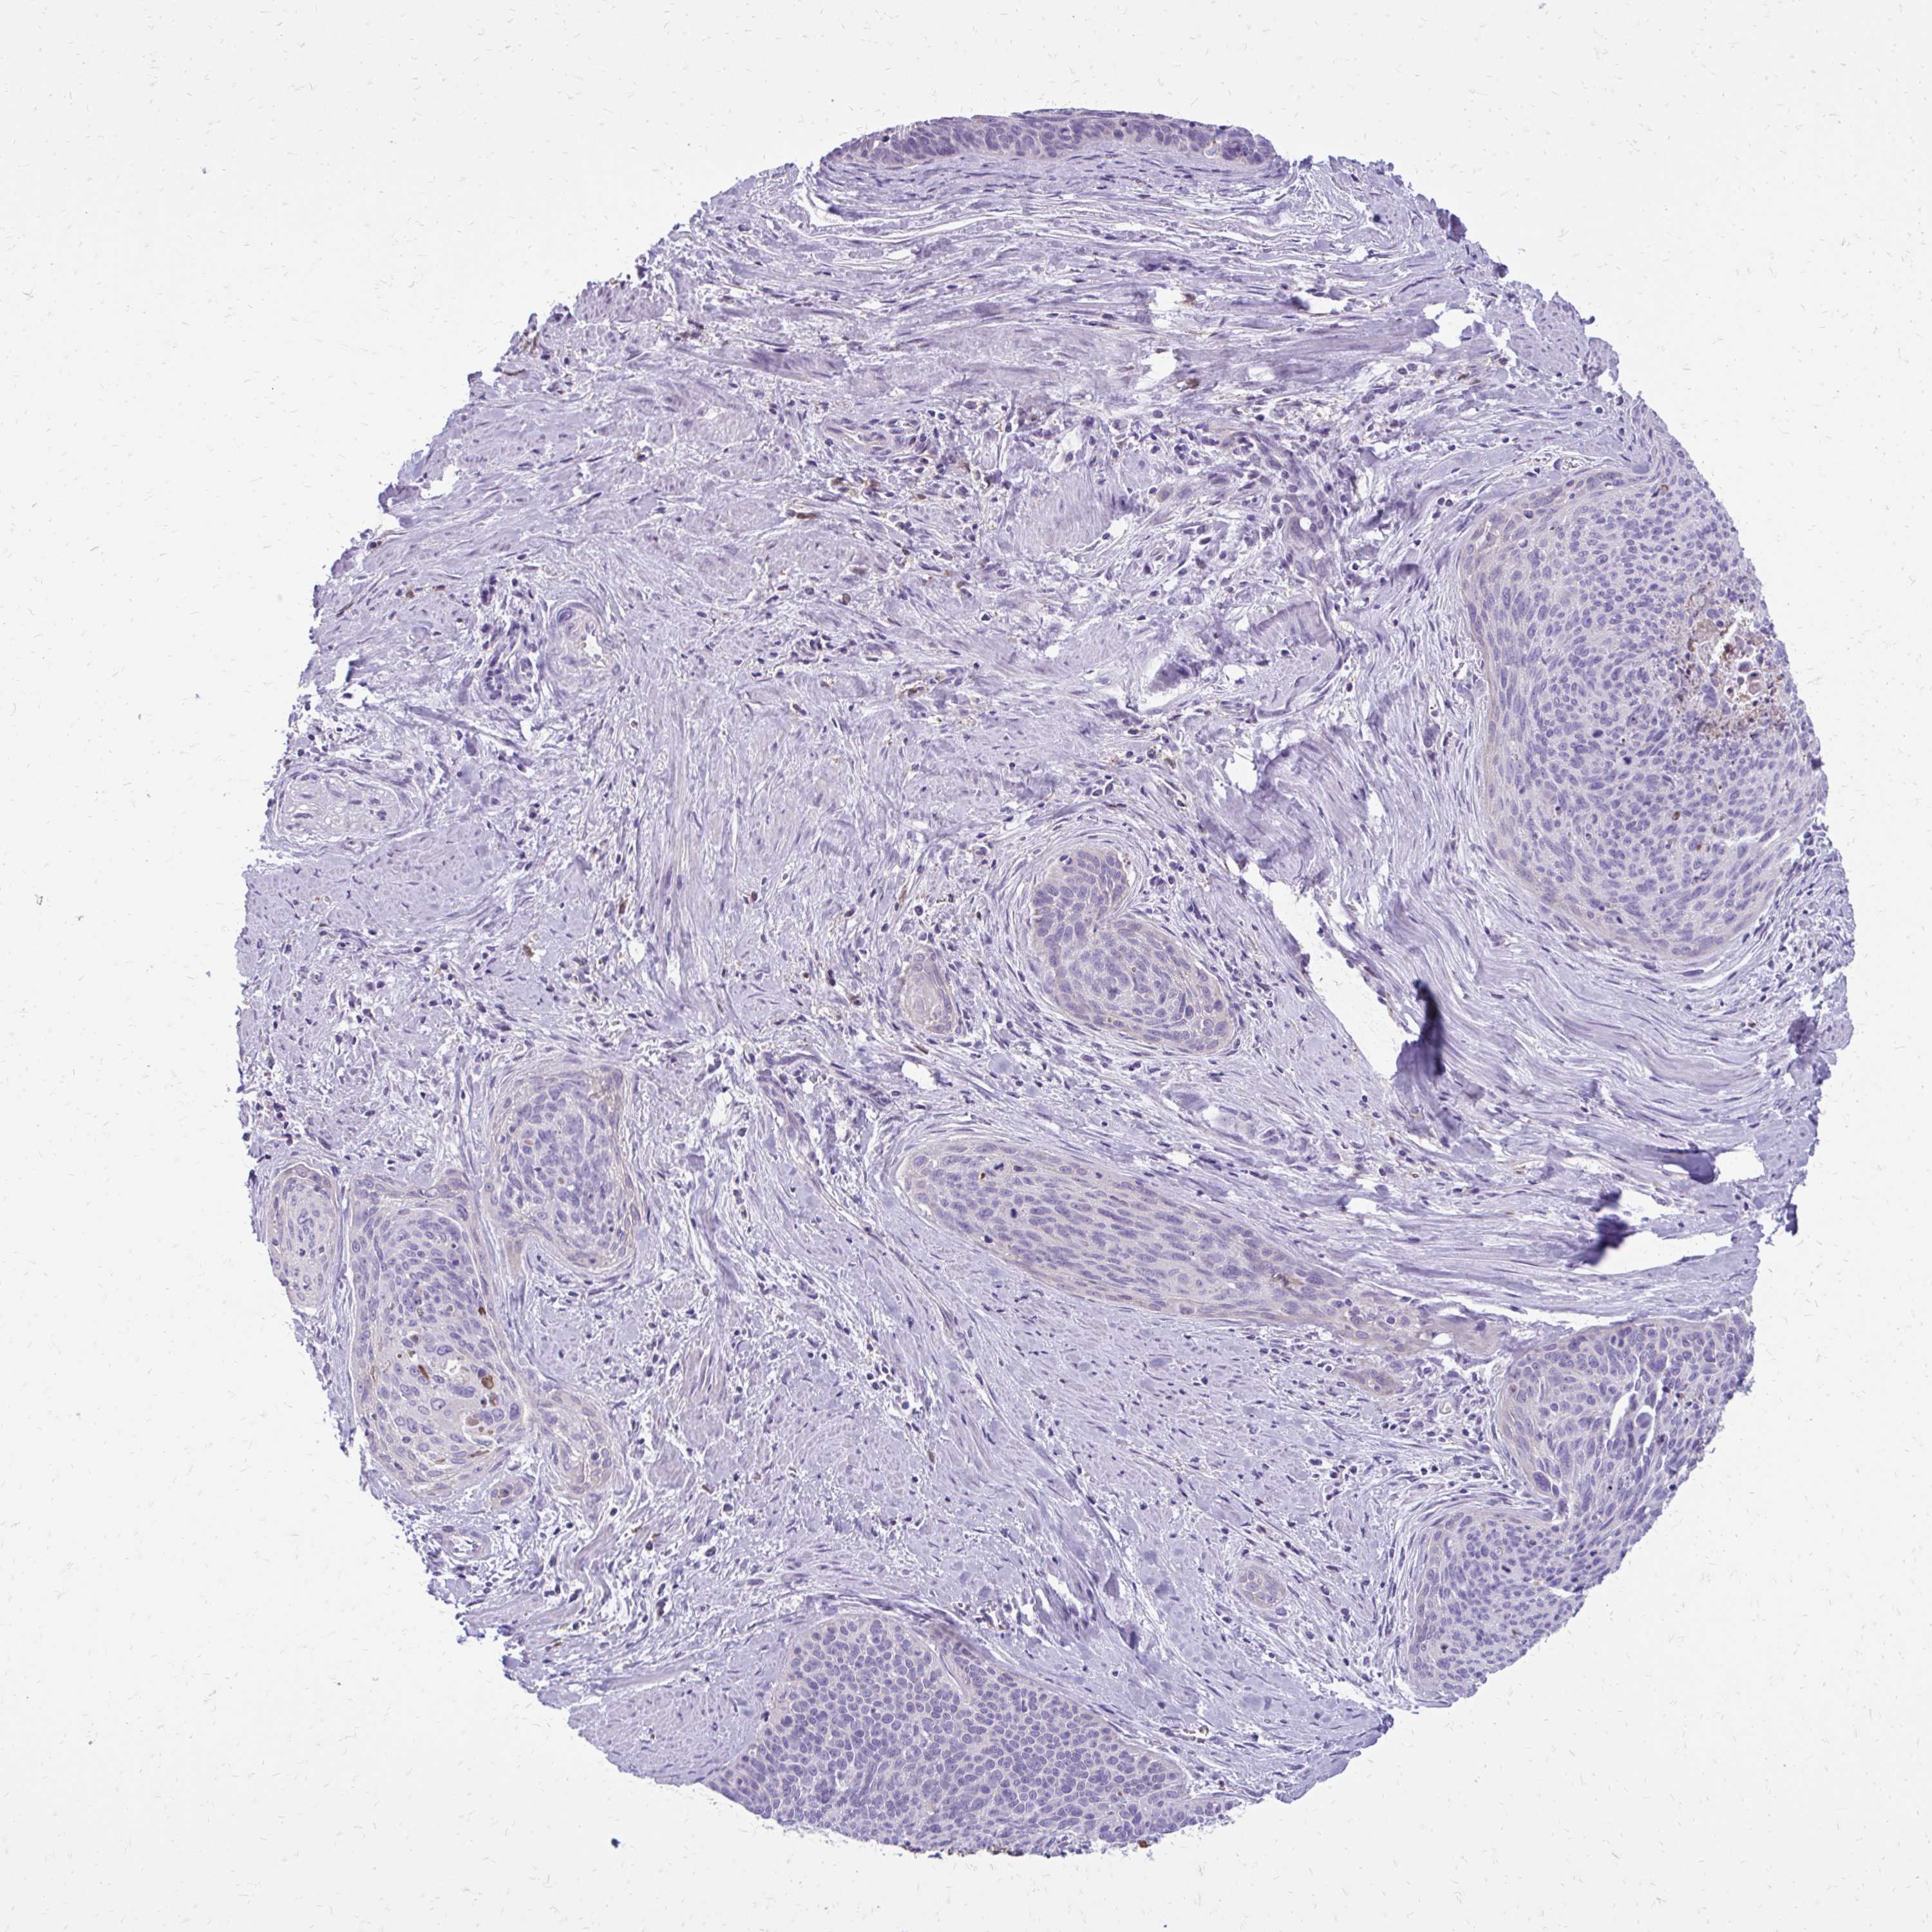

CERVICAL CANCER - Protein expressioni

A mouse-over function shows sample information and annotation data. Click on an image to view it in a full screen mode. Samples can be filtered based on level of antibody staining by selecting one or several of the following categories: high, medium, low and not detected. The assay and annotation is described here.

Note that samples used for immunohistochemistry by the Human Protein Atlas do not correspond to samples in the TCGA dataset.

Antibody stainingi

Antibody staining in the annotated cell types in the current human tissue is reported as not detected, low, medium, or high, based on conventional immunohistochemistry profiling in selected tissues. This score is based on the combination of the staining intensity and fraction of stained cells.

Each image is clickable and will lead to virtual microscopy that enables deeper exploration of all samples and also displays staining intensity scores, fraction scores and subcellular localization as well as patient and tissue information for each sample.

Antibody HPA060278

Staining

High

Medium

Low

Not detected

Intensity

Strong

Moderate

Weak

Negative

Quantity

>75%

75%-25%

<25%

None

Location

Nuclear

Cytoplasmic/membranous

Cytoplasmic/membranous,nuclear

Squamous cell carcinoma, NOS

Adenocarcinoma, NOS